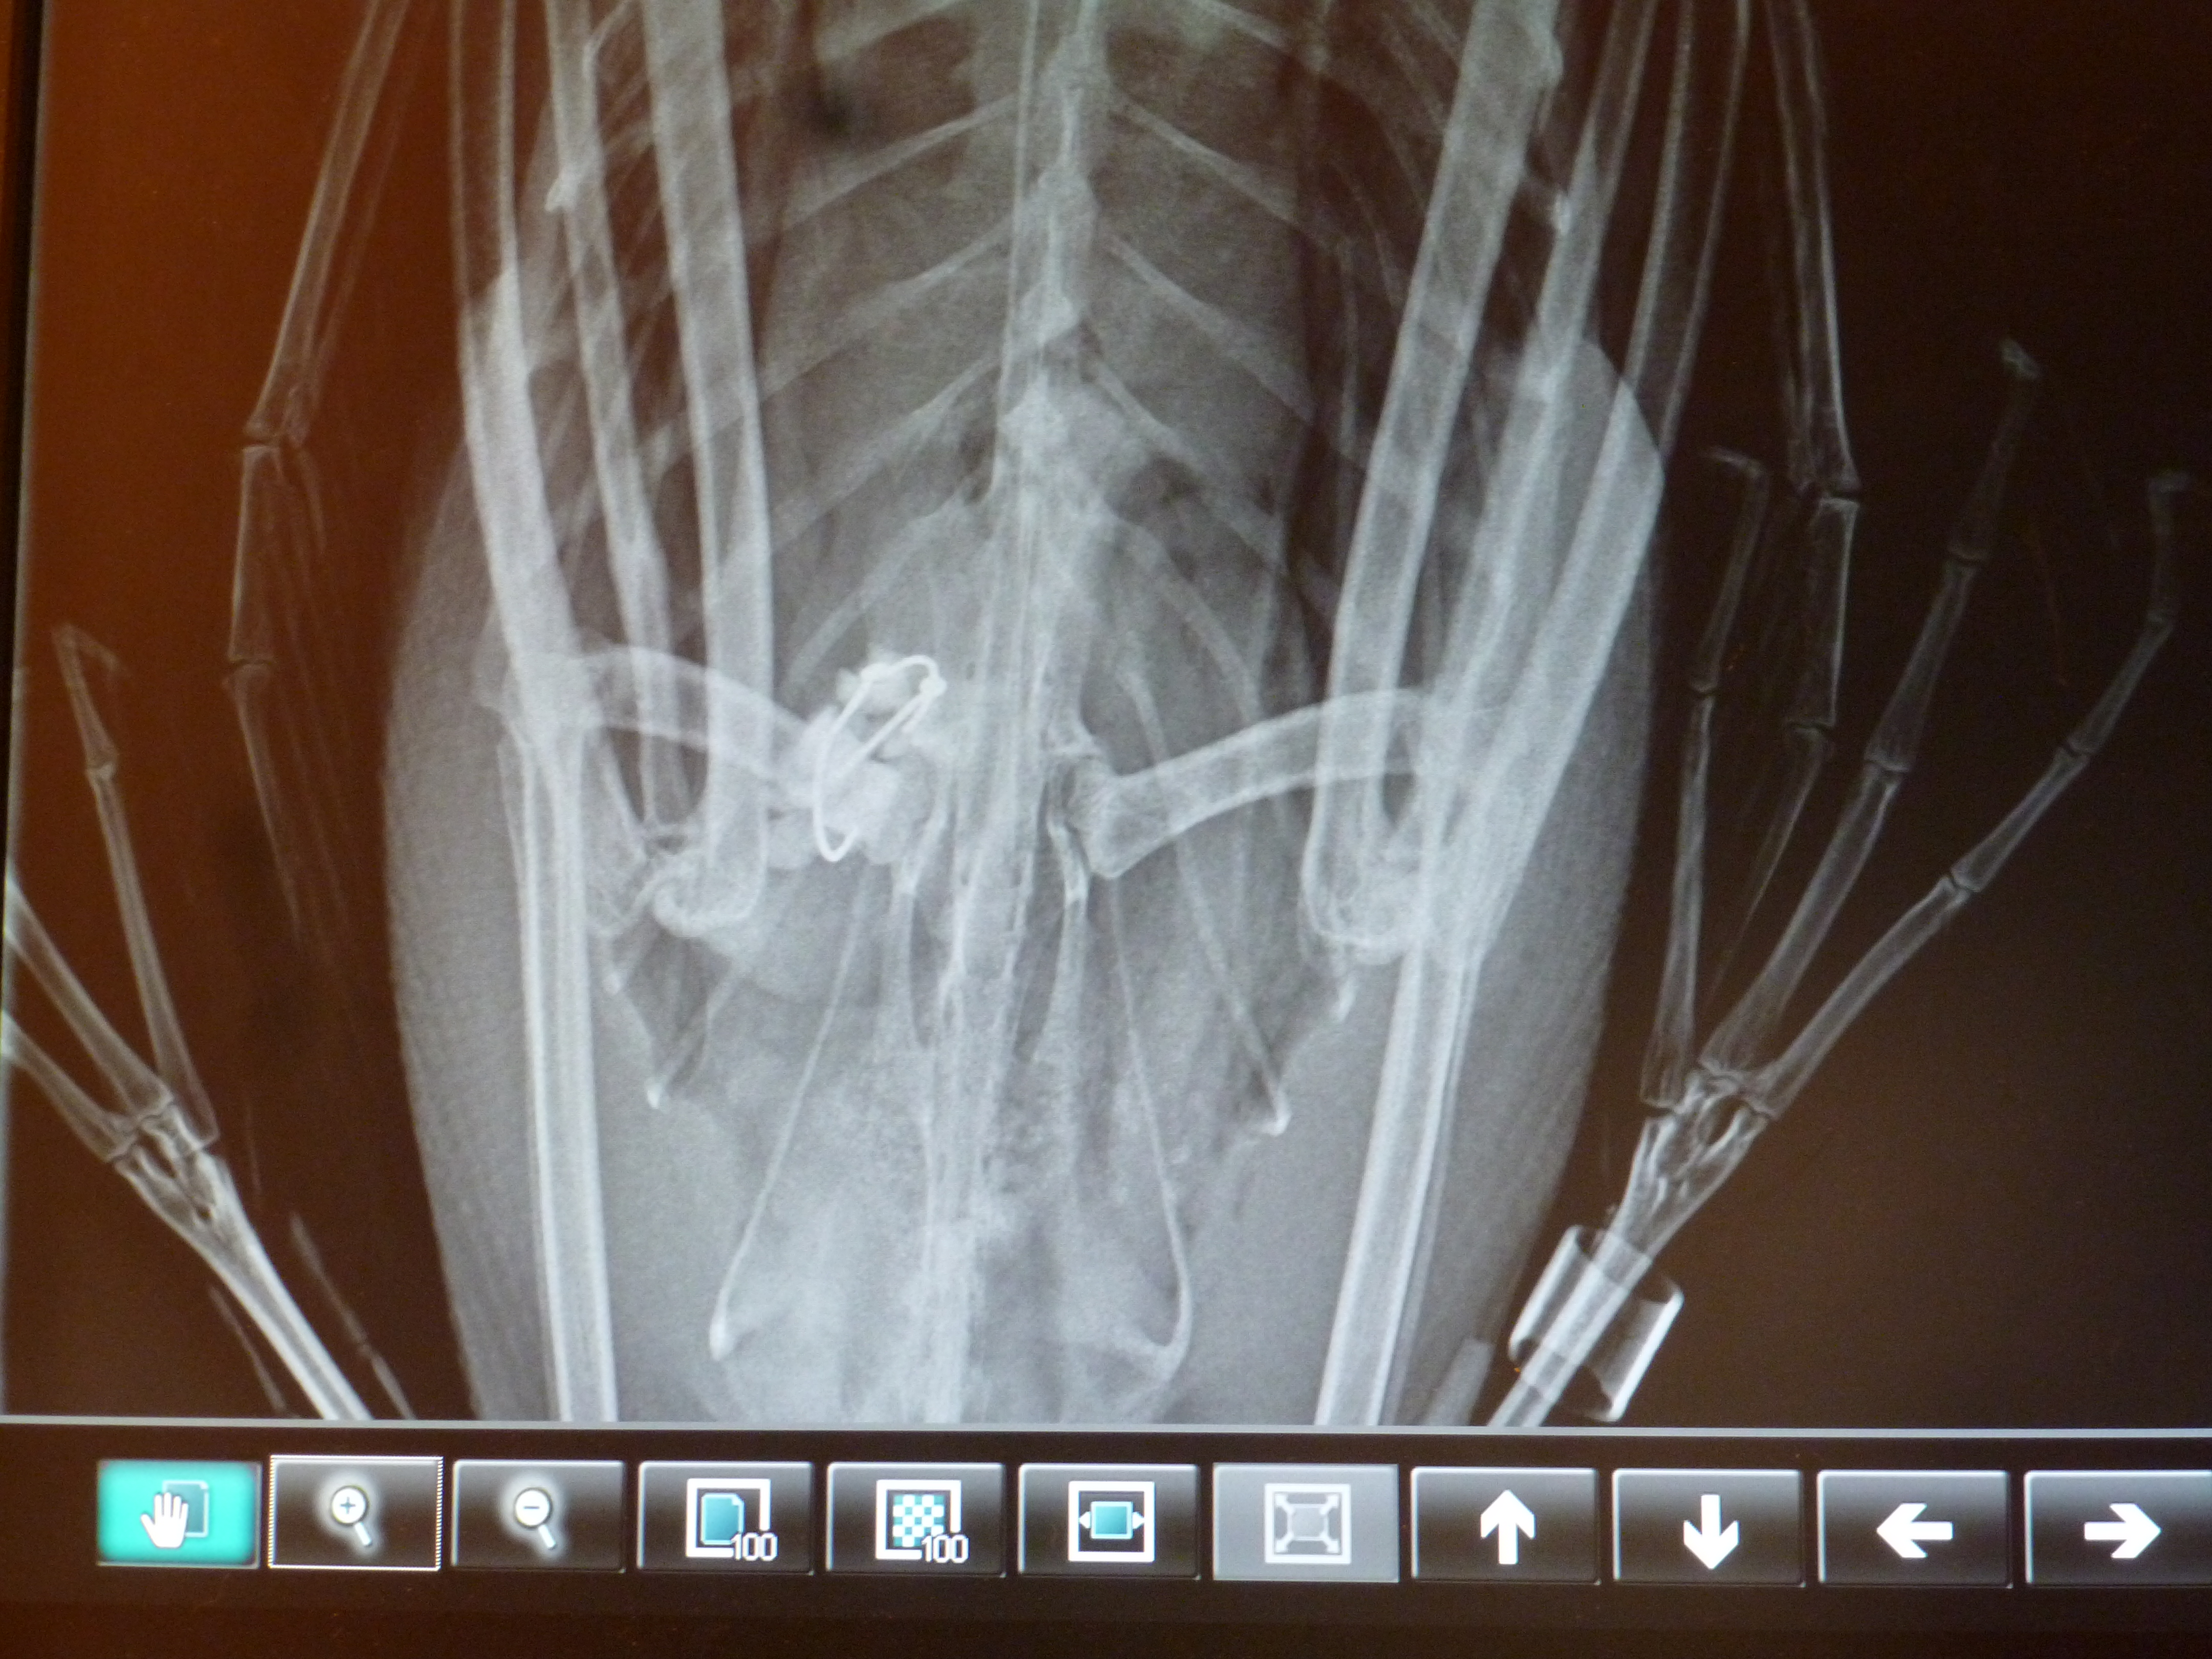

Initial x-rays revealed not just one hook, but two hooks similar to a rig for walleye fishing. One of the hooks had already made its way deep into the proventriculus. The proventriculus is one part of two parts of a bird’s stomach. It has very acidic pH which softens food to make it easier for the bird to digest. There was also a spot on the x-ray which could’ve been a lead sinker or a rock. If it was indeed a lead sinker, the possibility of lead poisoning was highly likely.